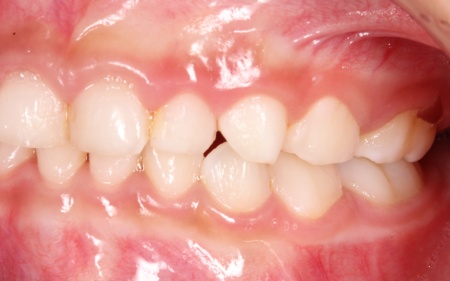

治療後

治療中は、スクリューを少しずつ回すことで顎の骨が徐々に横方向に拡大されていき、永久歯が生えるためのスペースを十分に確保することができました。

拡大治療が完了したあとは、顎の状態を安定させるためのリテーナー(保定装置)を装着し、治療を終了しています。